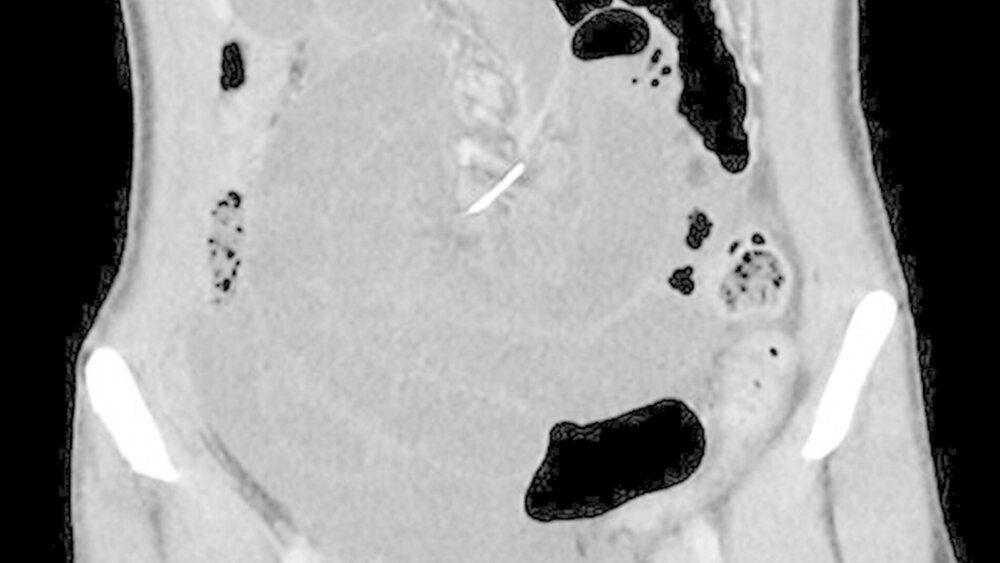

Wie die Ärzte bei der zweiten Untersuchung feststellten, hatte sich das Bauchfell entzündet. Das CT zeigte einen dünnen Metalldraht an der Mesenterialwurzel, also an der Stelle des Dünndarms, an der das Bindegewebe mit der Bauchwand verwachsen ist (Abbildung 1).

Der Draht hatte den Dünndarm durchbohrt und einen Darmabschnitt aufgespießt

Die Notfall-OP förderte schließlich einen sieben Zentimeter langen Draht zutage, wie er für kieferorthopädische Zahnklammern verwendet wird (Abbildung 2). Der Draht hatte den Dünndarm durchbohrt und einen anderen Darmabschnitt aufgespießt. Dies führte dazu, dass der Darm sich nicht mehr frei bewegen konnte, und es kam zu einer Darmverschlingung rund um den Draht, der die Achse für dieses Knäuel bildete, um die sich der Volvulus entwickelte.